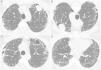

Chest CT images showing peripheral cysts pattern with honeycomb at the lung bases with an intracavitary nodule positioned anteriorly in the upper left lobe (A) that shifts position when the patient's decubitus is changed (B) (arrows). In C and D, small intracavitary nodules are visible inside cysts in the right lung (arrows).

Laboratory test results were normal. A chest X-ray showed diffuse bilateral basal reticular infiltrates and nodular opacity in the left upper lobe. Computed tomography (CT) demonstrated peripheral cystic pattern with thick wall and basal honeycomb, and multiple intracavitary nodules of various sizes, the largest located in the left upper lobe. The larger nodule showed variation in position as the patient's decubitus was changed (Fig. 1), suggesting the diagnosis of aspergilloma (fungus ball). Bronchoalveolar lavage (BAL) was performed and demonstrated the absence of active or residual bleeding. Gram staining of the BAL sample showed paired gram cocci. The study of malignant cells, acid-fast staining and common bacterial culture were negative. Analysis of BAL fluid showed the presence of septate and branched hyphae and positivity for galactomannan (9.26ng/mL; normal, <0.5ng/mL). Serology results were negative for HIV, hepatitis B, and hepatitis C and normal for rheumatoid factor, antinuclear factor, and antineutrophil cytoplasmic antibody.

This patient was diagnosed with saprophytic aspergillosis (aspergilloma) in honeycomb cysts based on imaging characteristics • mainly the characteristic shift of intracavitary nodule positions as the patient's decubitus was changed•along with the demonstration of fungus and positivity for galactomannan, with high values on BAL fluid analysis. The diagnostic hypothesis for the underlying pulmonary disease that caused cysts and honeycomb included pulmonary idiopathic fibrosis, asbestosis, chronic hypersensitivity pneumonia and combined fibrosis and emphysema. The patient was discharged from the hospital with oral itraconazole and levothyroxine, and was managed on an outpatient basis.

Recognition of typical aspergilloma signs is of paramount importance. On CT, the presence of an intracavitary nodule or mass that hangs down as the patient's decubitus is changed strongly suggests this diagnosis. Other findings include the “air crescent sign,” a sponge-like appearance, amorphous calcification within the lesion, and adjacent pleural thickening.